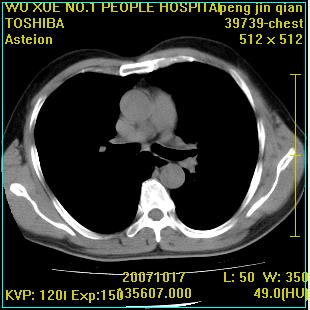

标题: CT10148:男,56岁,咳血。 [打印本页]

标题: CT10148:男,56岁,咳血。

左肺上叶尖后段较大团块影,边缘光滑,内见不规则裂隙样空洞,周围明显见细小结节及渗出,与肺门方向结构紊乱,另:左上叶尖段外侧 舌叶内侧 右上叶尖段及下叶背段均见片状致密影。考虑:继发性肺结核伴空洞形成!

左上肺后壁空洞,内壁不规则,可见壁结节;左上叶尖段外侧 舌叶内侧 右上叶尖段及下叶背段均见片状致密影。考虑:左肺肺癌并两肺继发性肺结核?

以下是引用卜一在2007-10-22 16:36:00的发言:[br]左肺上叶尖后段较大团块影,边缘光滑,内见不规则裂隙样空洞,周围明显见细小结节及渗出,与肺门方向结构紊乱,另:左上叶尖段外侧 舌叶内侧 右上叶尖段及下叶背段均见片状致密影。上腔静脉后淋巴结肿大,内有钙化。考虑:继发性肺结核伴空洞形成!